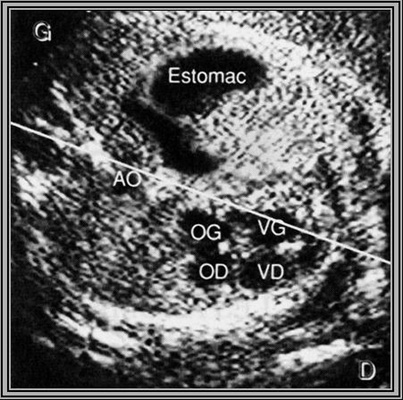

Dextrocardie

4 cavités